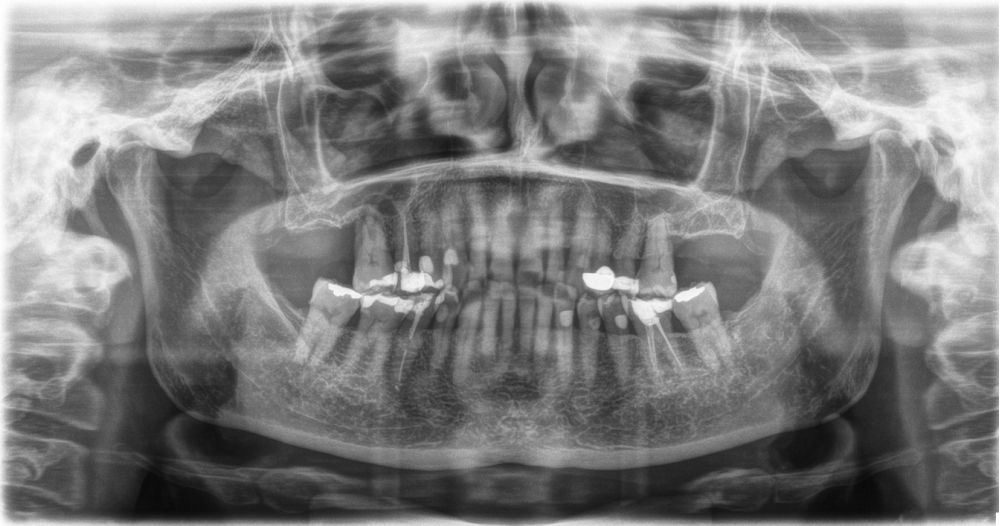

Material y método. Se ha llevado a cabo un estudio retrospectivo de pacientes tratados mediante implantes extracortos (5,5 y 6,5 mm de longitud) colocados mediante elevación transcrestal sin el uso de injerto. Como variables principales se han estudiado: la pérdida ósea crestal de los implantes y la ganancia en altura sobre el ápice. Como variable secundaria se ha estudiado la supervivencia de los implantes.

Resultados. Fueron reclutados 13 pacientes en los que se insertaron 30 implantes. Una vez insertados y cargados los implantes, la altura media final fue de 9,68 mm (+/- 2,66), lo que supone una ganancia promedio de 5 mm. A los 10 años, se observó una disminución media de la altura ósea ganada en los implantes en conjunto de 0, 29 mm (+/- 0,77). La media de la pérdida ósea mesial fue de 0,73 mm (+/- 0,75 mm) y la media de la pérdida ósea distal fue de 0,98 mm (+/- 1,2 mm). La supervivencia fue del 100%.

Material and methods. A retrospective study of patients treated with extra-short implants (5.5 and 6.5 mm in length) placed by transcrestal elevation without the use of a graft was carried out. The main variables studied were: the crestal bone loss of the implants and the gain in height above the apex. Implant survival was studied as a secondary variable.

Results.Thirteen patients were recruited and 30 implants were inserted. Once the implants were inserted and loaded, the mean final height was 9.68 mm (+/- 2.66), which represents an average gain of 5 mm. At 10 years, there was a mean decrease in the overall bone height gain of the implants of 0.29 mm (+/- 0.77). The mean mesial bone loss was 0.73 mm (+/- 0.75 mm) and the mean distal bone loss was 0.98 mm (+/- 1.2 mm). Survival was 100%.

Los senos tratados con la técnica de elevación transcrestal sin material de relleno muestran un incremento de entre 2,5 mm12,13 hasta 4.4 mm14,15 en la altura ósea lograda sobre el ápice y una supervivencia de los implantes que se sitúa entre un 94 y un 100%16-17. En este trabajo se presenta un estudio retrospectivo donde se ha evaluado la inserción de implantes extracortos (5,5 y 6,5 mm) en zonas posteriores maxilares mediante la técnica de elevación de seno transcrestal con la fresa de ataque frontal sin la utilización de material de injerto, con un tiempo de seguimiento de 10 años para poder objetivar el comportamiento de los implantes a largo plazo y de la técnica empleada.